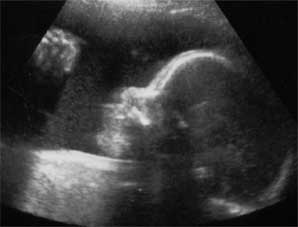

Now for the fun part... Pictures!!

The picture on the left is of her face, straight on. The left side of her face is in shadow, but you can clearly see her right eye, her nose, and her lips. Isn't that amazing?! Our little Ella has a face! I can't wait until the 4-D ultrasound. One good thing about having plenty of amniotic fluid is that the ultrasound pictures come out really good.